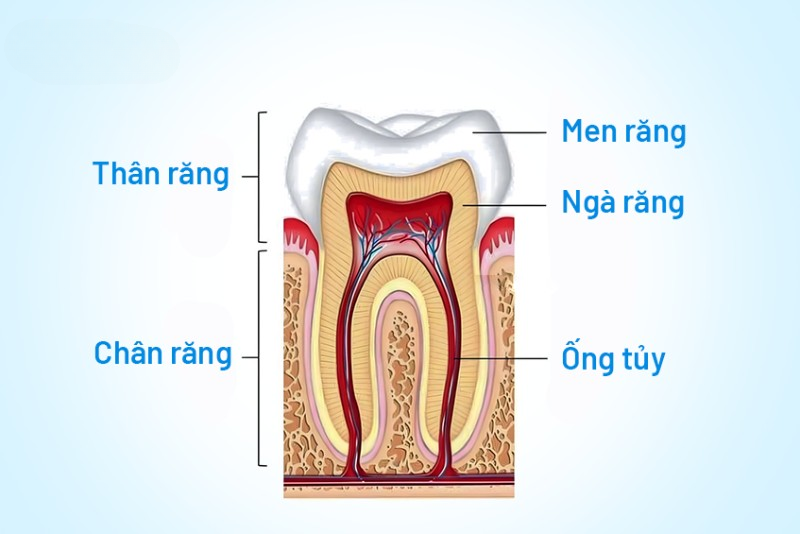

Cấu tạo tủy răng và vai trò của tủy răng

Để hiểu rõ viêm tủy răng là gì, cần nắm được cấu tạo cơ bản của răng gồm 3 phần chính:

Men răng: Lớp ngoài cùng bảo vệ răng

Ngà răng: Lớp trung gian dẫn truyền cảm giác

Tủy răng: Phần lõi chứa dây thần kinh và mạch máu

Tủy răng có vai trò:

Nuôi dưỡng răng phát triển khỏe mạnh

Cảm nhận nhiệt độ và lực nhai

Duy trì sự sống của răng

Khi tủy bị viêm hoặc chết tủy, răng sẽ trở nên yếu, giòn và dễ gãy vỡ hơn.